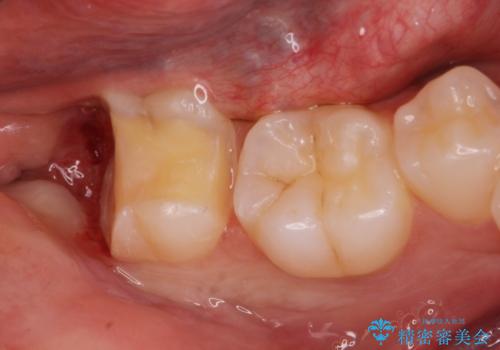

- 親知らずが虫歯になっている気がするとの事で来院。

親知らずとその手前の歯が虫歯になっていました。

先に虫歯を徹底的に取り除き親知らずを抜歯してe-maxインレーで治療を行いました。